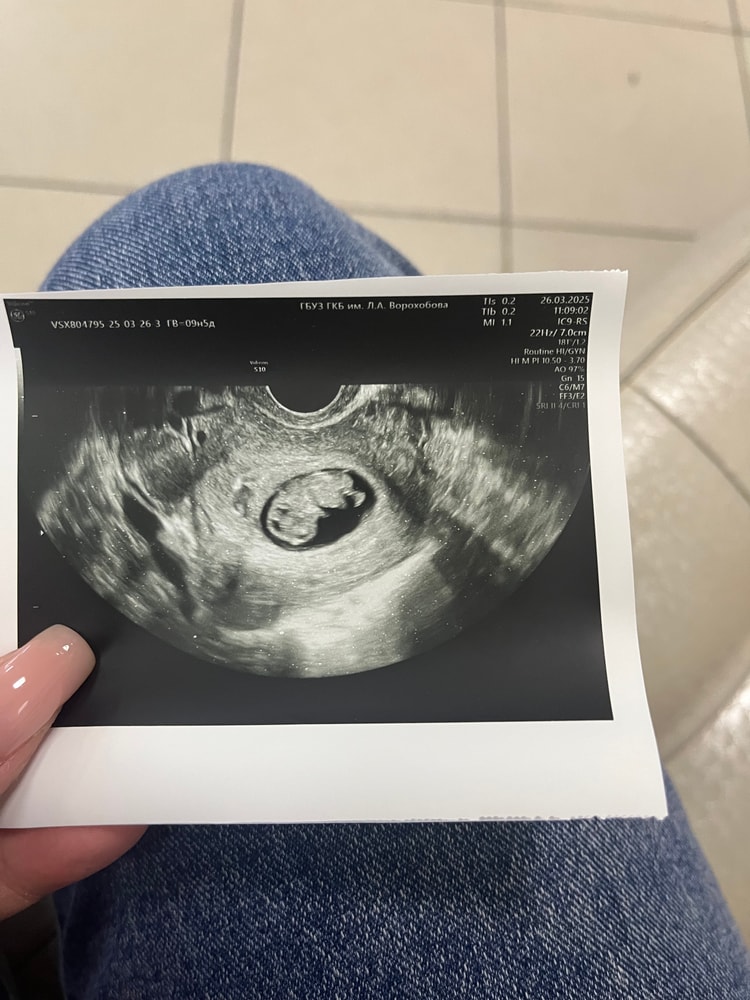

9+5 недель

УЗИСходила на узи по направлению гинеколога, чтобы встать на учет. Нуу, про бесплатное узи и говорить нечего, спасибо хоть фоточку дали 😅 параметры никакие не знаю, жду заключение в личный кабинет. Но, боже, мое сердце просто остановились, когда мне показали какой он уже большой ❤️ Уже хомяк, а не креветка) Беспокоит немного, что плодное яйцо все-таки не особо большое, но вроде место есть)